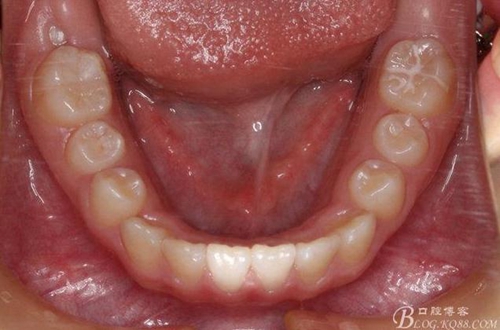

矯治第6個月復診:前牙反咬合已經(jīng)完全解除,上頜前牙也進一步排齊了。后牙咬合接觸改善。

矯治第7個月復診:磨牙已有咬合接觸。上頜兩個6貼粘貼頰面管,矯治裝置成為真正的“2×4”矯治器。因為上頜兩個3唇側(cè)錯位為完全弓外牙,所以在上頜弓絲上彎制了彎曲進行避讓。兩個頰面管的近中設置了“阻擋曲”,目的是使上頜前牙進一步唇移,同時為側(cè)方牙齒的萌出創(chuàng)造空間。停止使用固定式低位唇弓Activator。